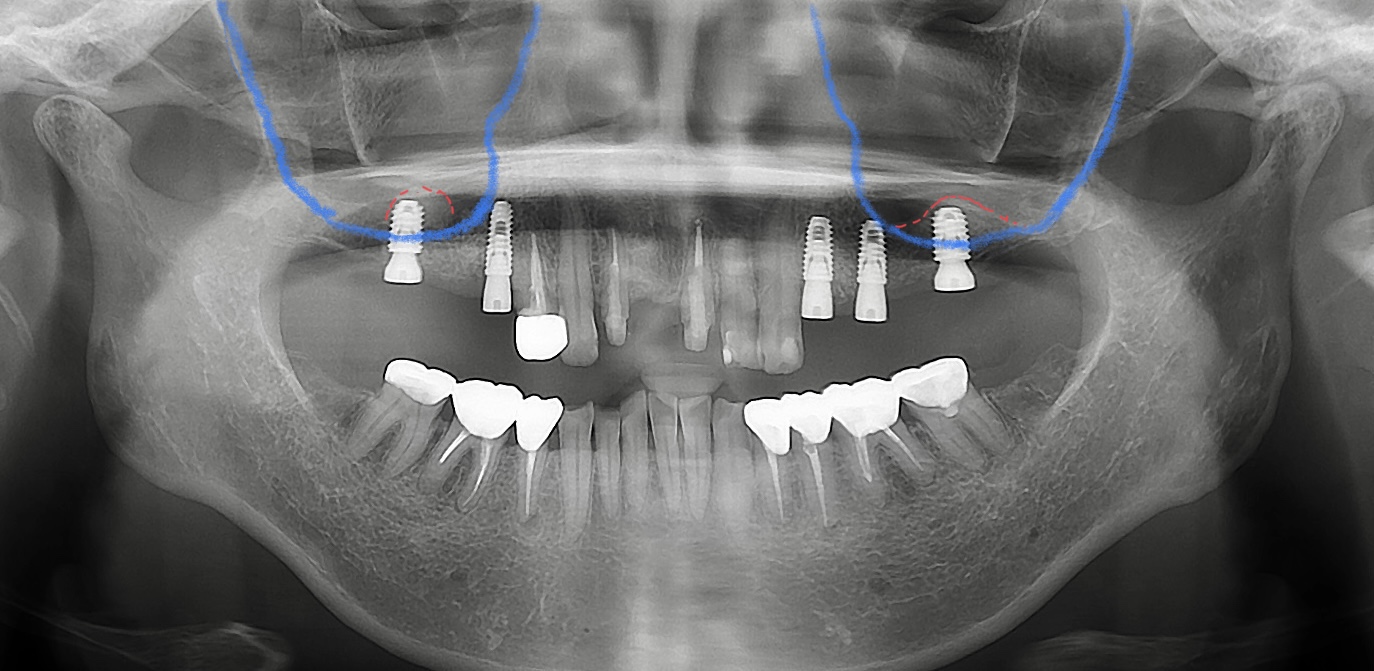

〈サージカルガイド(インプラントガイド)とは〉

インプラントを埋入する際に、計画通りの正確な位置に埋入する為に使用するものです。

写真は昨日オペをされた患者さまのサージカルガイドで、消毒液によって色が染まってしまいましたが、元々は透明に近いです😬

こちらのサージカルガイドを使用したことで、歯茎を切ること無くソケットリフトでインプラントを埋入することができました🦷✨歯茎を切らないので術後の腫れも少ないです。

青い部分は上顎洞、赤い部分はソケットリフトによって持ち上げられた箇所です💁